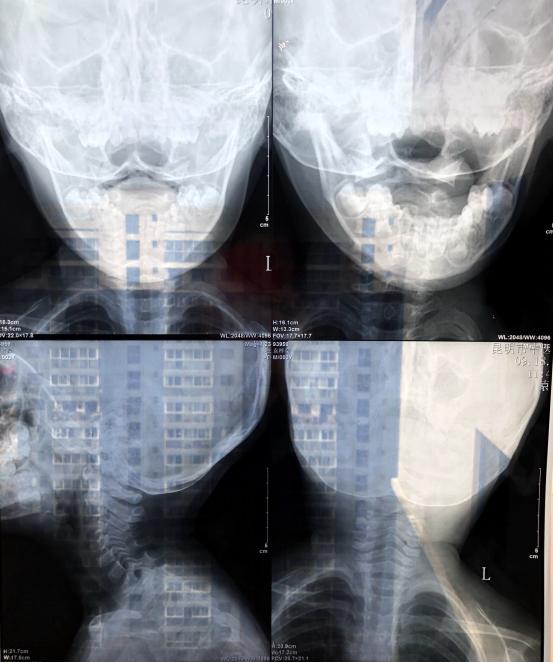

【看图说病】是唐都医院脊柱神经外科为了方面患者异地就诊,根据患者影像学检查资料给出相应诊断和建议的栏目。本期是一位外伤后在低头的时候会头疼的患者。

患者今年三岁,有外伤史(从床上摔下来)现在低头的时候头会疼。

李维新 教授:从患者的CT来看,没有明显的骨性结构异常,应该没有大碍。

李维新 教授:从现在的情况来看,没有什么明显的异常,也没有治疗的必要,但是需要加强观察,出现异常以后及时到医院就诊。